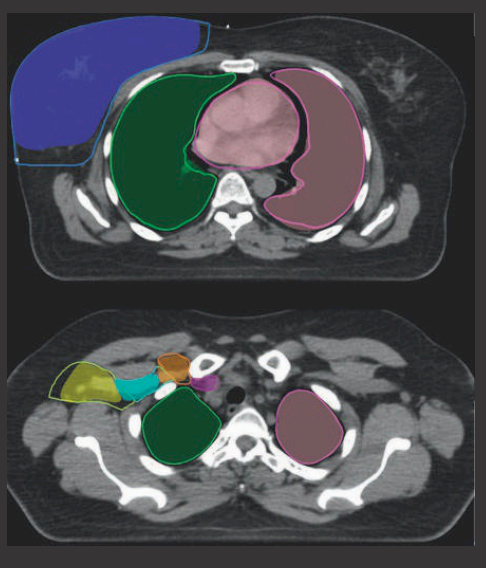

Na haar afstuderen ging Bakx verder als trainee van de post-masteropleiding Qualified Medical Engineer om haar planningsmethodiek ook uitgebreid klinisch te testen. Ook onderzocht de PDEng-student of het intekenen van organen van borstkankerpatiënten ook snel, accuraat en betrouwbaar kan met de computer.

“Als mensen met borstkanker bestraald moeten worden, bekijkt de radiotherapeut wat precies nodig is: hoeveel doses, hoeveel sessies, met welke frequentie? Vervolgens moeten we zorgen dat de behandeling technisch ook goed wordt uitgevoerd. Daarvoor hebben we beelden van de patiënt nodig in de houding van de bestraling. Nu gebruiken we nog CT-beelden, dat worden in de nabije toekomst ook vaker MRI-beelden. Op de beelden worden de organen heel precies ingetekend.

Vervolgens bootsen we in een soort flight simulator virtueel na hoe we willen bestralen: van welke kant en met welke intensiteit, zodat er zoveel mogelijk straling in de tumor komt en zo weinig mogelijk daar omheen.”

Ook voor het automatisch intekenen van de organen en kliergebieden ligt het model klaar en komt er nu een klinische pilot. Nienke Bakx is blij dat wat ze in haar master en haar QME-periode gedaan heeft nu echt de klinische praktijk in gaat.